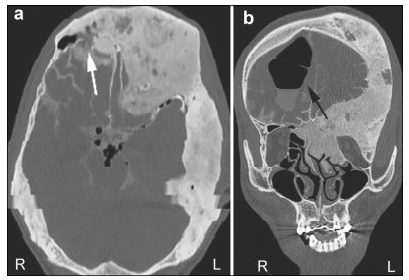

The patient underwent craniotomy fistula repair sur-gery. A coronal incision was made and a pericranium flap was prepared for cranial base repair. The bone window was 7 cm × 15 cm. We explored the entire anterior cranial base and located the fistula to the posterior wall of the right frontal sinus as demonstrated by the preoperative CT cisternogram. The pericranium was folded to cover the defect and then sutured to the cranial base dura. The bone flap was repositioned and fixed using standard techniques. To increase the cranial cavity and decrease the intracranial pressure, the excised bone flap was contoured to be thinner before it was placed back (Figure 3). As the patient’s sight was good in both eyes, optic nerve decompression was not performed although the left optic nerve was evidently compressed by expanded bones (Figure 1).

| Figure 3 A CT scan demonstrating a contoured bone and enlarged cranial cavity. (a, b) Before the fistula repair surgery. (c, d) After the fistula repair surgery. |

The second factor was increased intracranial pressure associated with CFD that might contribute to CSF rhinorrhea. In this case, a CT scan demonstrated significant thickening and expansion of multiple skull bones, decreasing the cranial cavity (Figure 1). However, before the head trauma, this patient did not have symptoms associated with increased intracranial pressure, including headache, nausea and vomiting. This suggested that before the trauma, the patient’s intracranial pressure was well compensated. However, as the cranial cavity was decreased after trauma, this compensation for a higher intracranial pressure was constrained. During the period of trauma, both the swelling of the brain and pneumocephalus might have contributed to the increased intracranial pressure. Without good compensation ability, the patient’s intracranial pressure increased. Although the intrac-ranial pressure measured by lumber puncture before the fistula repair surgery was normal, this might have been associated with an alleviation of the swelling brain after a forty-day recovery and the discharge of CSF through the fistula. To increase the cranial cavity, we contoured the excised bone to be thinner before it was placed back during the fistula repair surgery. This treatment effect was satisfactory (Figure 3).